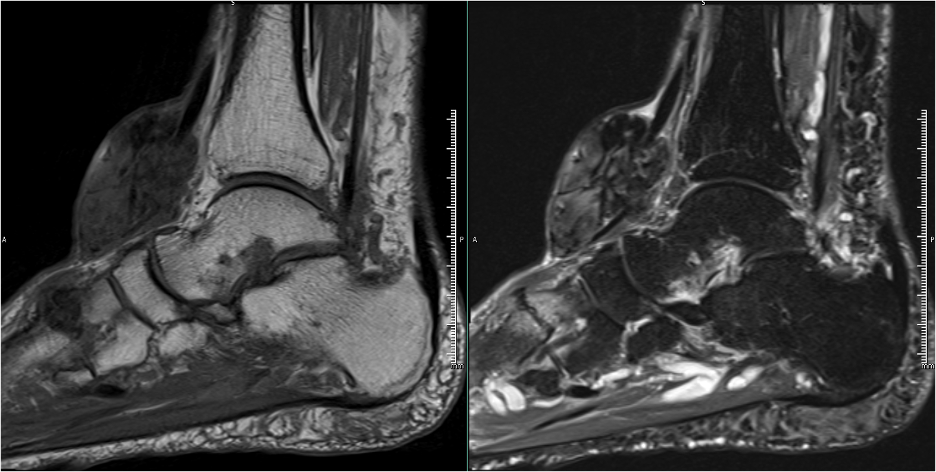

The patient received a referral to our clinic for consideration of soft tissue mass excision. An MRI revealed a 6.0 x 5.8 x 3.1 cm mass at the anterior ankle in close relation to the tibialis anterior and extensor hallucis longus tendons. The soft tissue mass was predominantly hypointense on T1- and T2-weighted images with no postcontrast enhancement (Figures 3-4).

Advanced imaging studies are beneficial when differentiating FTS from other soft tissue masses. MRI findings typically include a hypointense, well-defined lesion on T1- and T2-weighted images.6 The soft tissue mass in our case was similar to previously described FTS, with hypointensity on both T1- and T2-weighted images and no postcontrast enhancement. Our findings are similar to those of Ciatti and colleagues7 who described hypointensity on T1- and T2-weighted images for a mass at the anterior ankle capsule.